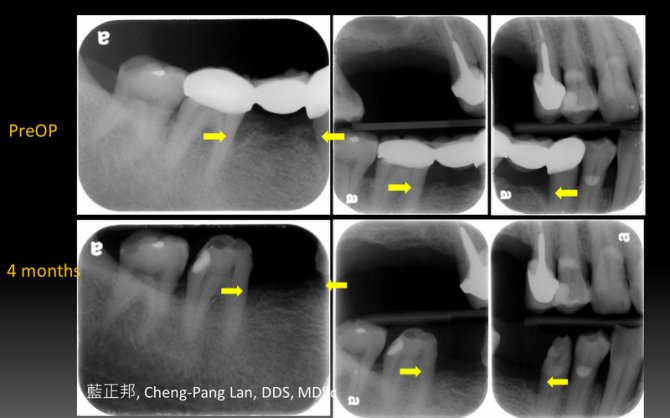

Guided Tissue Regeneration – Case E

This entry was posted in Periodontal Regeneration and tagged Autogenous bone, Collagen membrane, GTR, Intrabony defect. Bookmark the permalink.